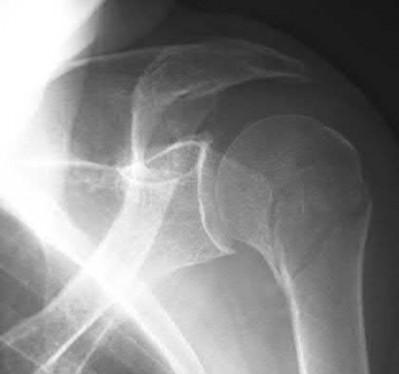

1036) A 68-year-old woman sustains the injury seen in Figure 189 following a fall. Careful neurologic and vascular examinations reveal no associated injury. What is the most common complication of surgical fixation with a locked plate and screw construct through a deltopectoral approach?

1. Infection

2. Axillary nerve palsy

3. Peri-implant fracture

4. Deltoid insertion detachment

5. Screw penetration of the articular surface Corrent answer: 5

Several studies have documented screw penetration through the articular surface as the leading complication with locked plate and screw fixation for displaced proximal humerus fractures. Axillary nerve palsy is rare but can be seen with a deltoid split approach. Whereas some loss of range of shoulder motion is expected following this injury, infection rates about the shoulder are in the 1% to 5% range. While a portion of the deltoid insertion is commonly taken down, complete deltoid insertion detachment has not been described.